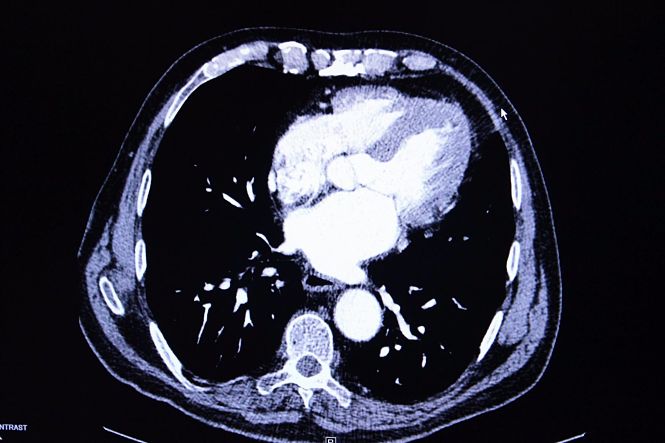

La niña sufre de un glioma difuso de la línea media con mutación H3 K27M, una enfermedad y condición incurable

La niña sufre de un glioma difuso de la línea media con mutación H3 K27M, una enfermedad y condición incurable que ha hecho que sus padres se dediquen a sus hijas "para hacer especial cada día", han asegurado. "Nuestra hija ha demostrado ser una niña fuerte, alegre, cariñosa y generosa que tiene unas enormes ganas de vivir", ha contado la familia Gonzalo Soler.